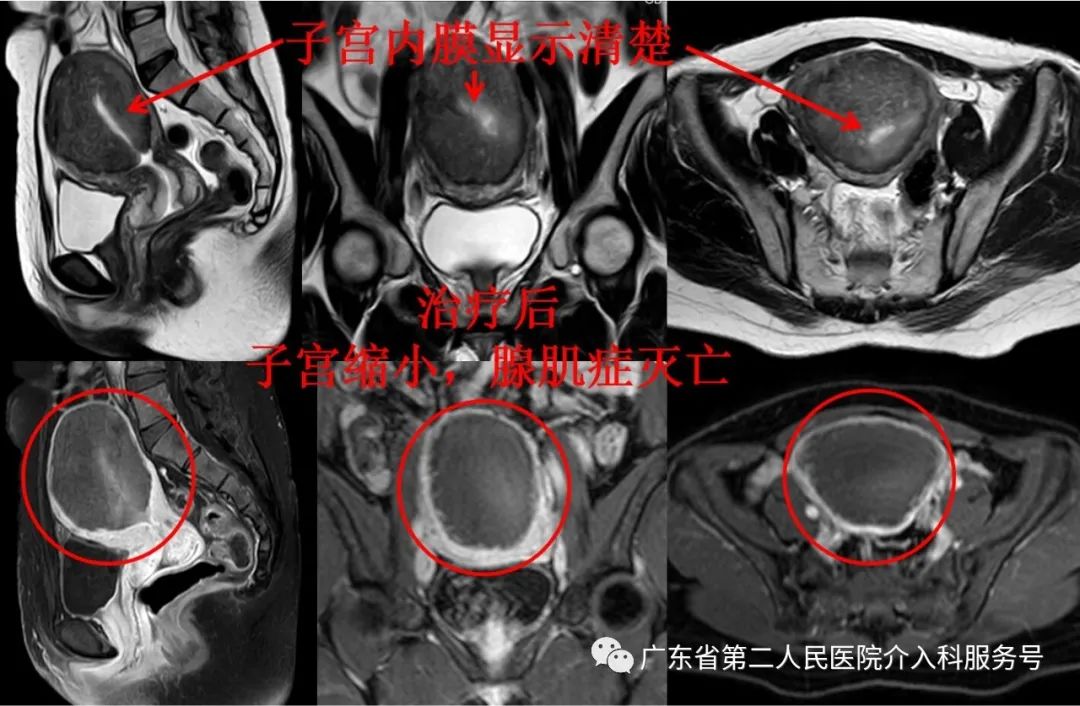

门诊磁共振检查:子宫巨大(148*101*89mm3),子宫腺肌症呈弥漫性分布(如下图)。

下图为治疗后3个月复查的磁共振图(子宫缩小,腺肌症灭亡,无血流)。